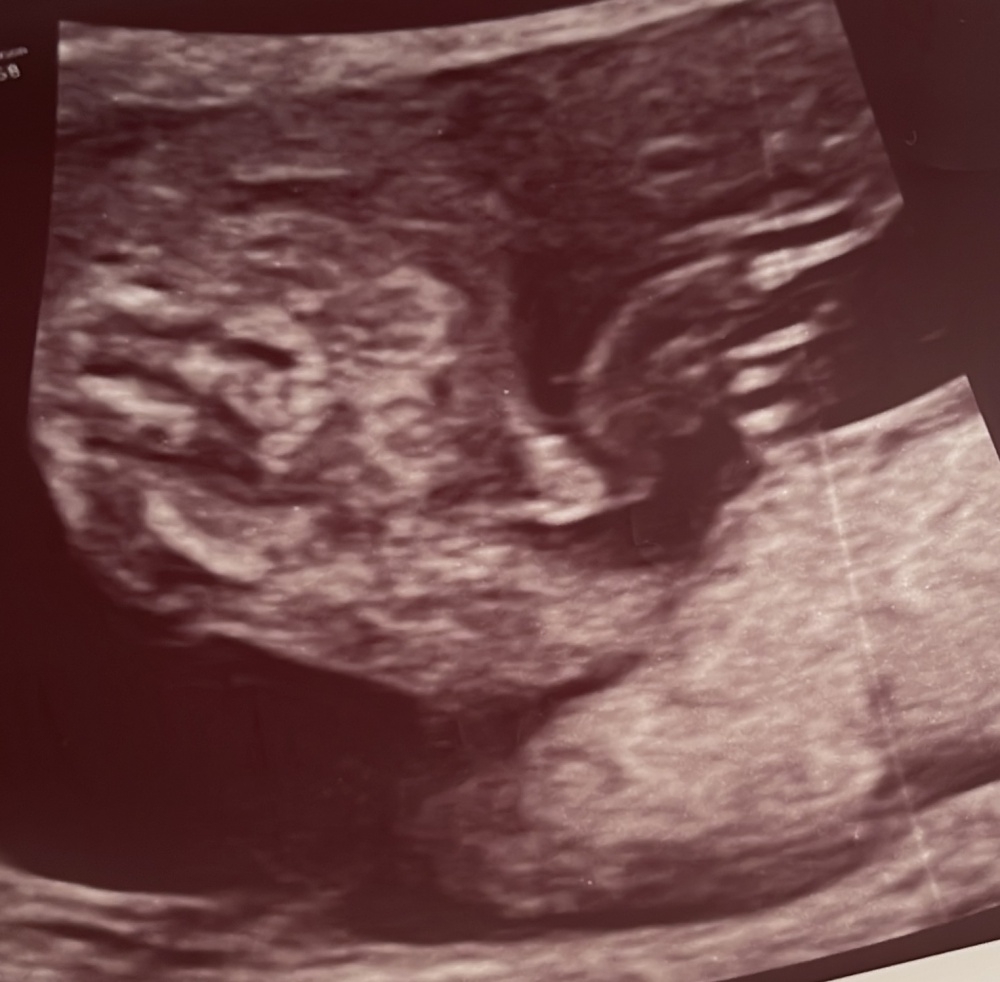

Könnt ihr auf dem Bild erkennen ob es ein Junge oder Mädchen wird? Ultraschall Bild ist von der 17+0.

Frauenärztin tendiert zu einem Jungen und hat gemeint dass man auf dem Ultraschallbild das Geschlecht erkennen kann.